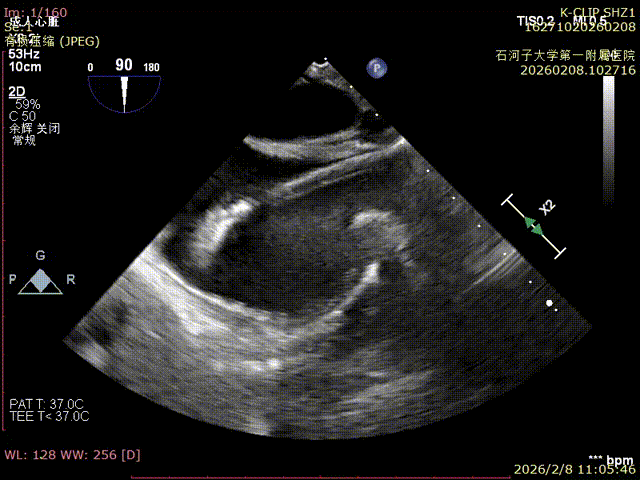

Echocardiographic Findings:Severe tricuspid regurgitation (4+; average vena contracta width, 12 mm). The regurgitation was predominantly anteroseptal and central, with a small posteroseptal component. During systole, the anterior and septal leaflets protruded slightly into the right atrium, with a protrusion height of 2.6 mm. A 6 mm gap was observed at the anteroseptal and central regions. Tricuspid annular dilatation was present (mean annular diameter, 40 mm), with a prominent gap at the anteroseptal region.

CTA evaluation: Tricuspid annulus dilatation. Diastolic tricuspid annulus circumference: 145.9 mm, area: 1648.8 mm². The right coronary artery (RCA) courses toward the atrial side; the shortest distance between the coronary artery and the annulus during diastole is approximately 2.14 mm, with the RCA deviated to the atrial surface.

Immediate Postoperative Echocardiographic Assessment: Tricuspid regurgitation was reduced from preoperative grade 4+ to grade 1+, the annulus diameter was reduced to 6.15 cm², and the leaflet coaptation was satisfactory.

Preoperative annulus area: 11.5 cm²

Postoperative annulus area: 6.15 cm²